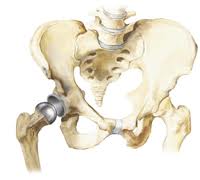

Originally, when I first went to Dr. Smith we addressed my lower back and cervical issues. I knew what was going to happen with those. But after my spine was straightened, I found my hip was popping out more and more. It put me down for lengths of time, rendering me unable to do my “back rehab” the way I was supposed to. It was so frustrating for me. Dr. Smith and I discussed it and he sent me to a doctor of orthopaedics that he highly respected, Dr. Michael Crovetti.

Dr. Crovetti is a powerhouse, young, sensitive, energetic and a genius when it comes to fixing hips. I was out of my hard neck brace only four days when I saw him in his office. There he took one look at my x-rays on the lightbox and said, “Yup, I see what’s wrong,” pointing at the deformity along the bone line. That was the good news, he knew what the problem was. The bad news was, “You’re gonna need a hip replacement soon.” I broke into tears. I felt so bad for him, it’s the first time I’ve ever cried in a doctors’ office. But it was the final blow. In less than two months I wouldn’t have the great insurance, and I wasn’t yet healed from my neck surgery. He looked at me and said almost apologetically, “I’m not trying to force you into anything you’re not ready to do, I’m just saying, to be out of pain, you’re gonna need a total hip replacement soon.”

Dr. Crovetti is an amazing doctor who understands not only the mechanics of your problem but brings to the operating table the reason each of his patients has for going through the surgery to get back in the game. As a former athlete sidelined because of a sports injury, he is VERY much aware of the sacrifices his patients have already made because of their condition. He truly wants you back in the game as soon as medically possible, to live your fullest life. I am in awe of his work. I was up and walking 3 hours after surgery and off the walker and no cane assistance in four weeks. And yes, I did ALL the rehab he prescribed for me, and then some! I WOULD DO IT ALL AGAIN IF I HAD TO… HE’S THAT GOOD!

Dr. Crovetti put in a ceramic hip which has yet to fail in clinical trials so he could not give me a specific end date for my hardware. He told me I could go back to water skiing if I wanted to, however Dr. Smith has already nixed that idea since he’s done all the other repair work. In 1978 my mother had her right hip replaced and was told that within ten years she’d have to have it replaced. She had the “old style” but never did need to have it redone.